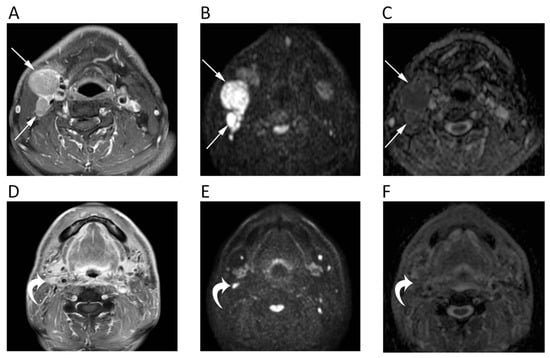

3. Head and Neck

11. Prostate

12. Lymph Nodes and Spleen